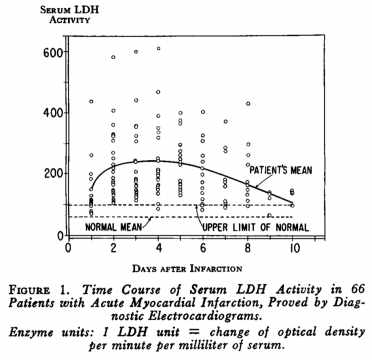

1956年

此前,急性心肌梗塞的诊断依赖于心电图,这导致很多病人被漏诊了。血清标志物,例如白细胞计数和红细胞沉降率等指标也在使用,但都不够特异。S.J. Adelstein和同事发现急性心梗患者锌浓度下降,乳酸脱氢酶和苹果酸脱氢酶的浓度上升。其中乳酸脱氢酶的表现尤为突出,这使得血清标志物诊断急性心梗成为可能,加速了临床诊断并且使诊断更加精确。